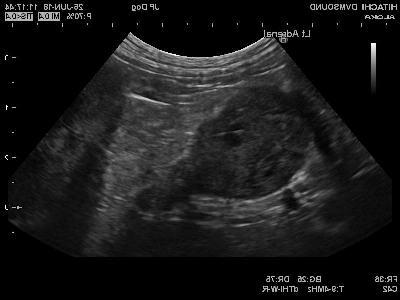

Many work-ups include screening for infectious disease and imaging (such as chest or abdominal imaging) to check for tumours, inflammatory disease, or other trigger factors. This step matters because treating the trigger can change the outcome, and because immunosuppressive drugs can make some infections harder to control.7